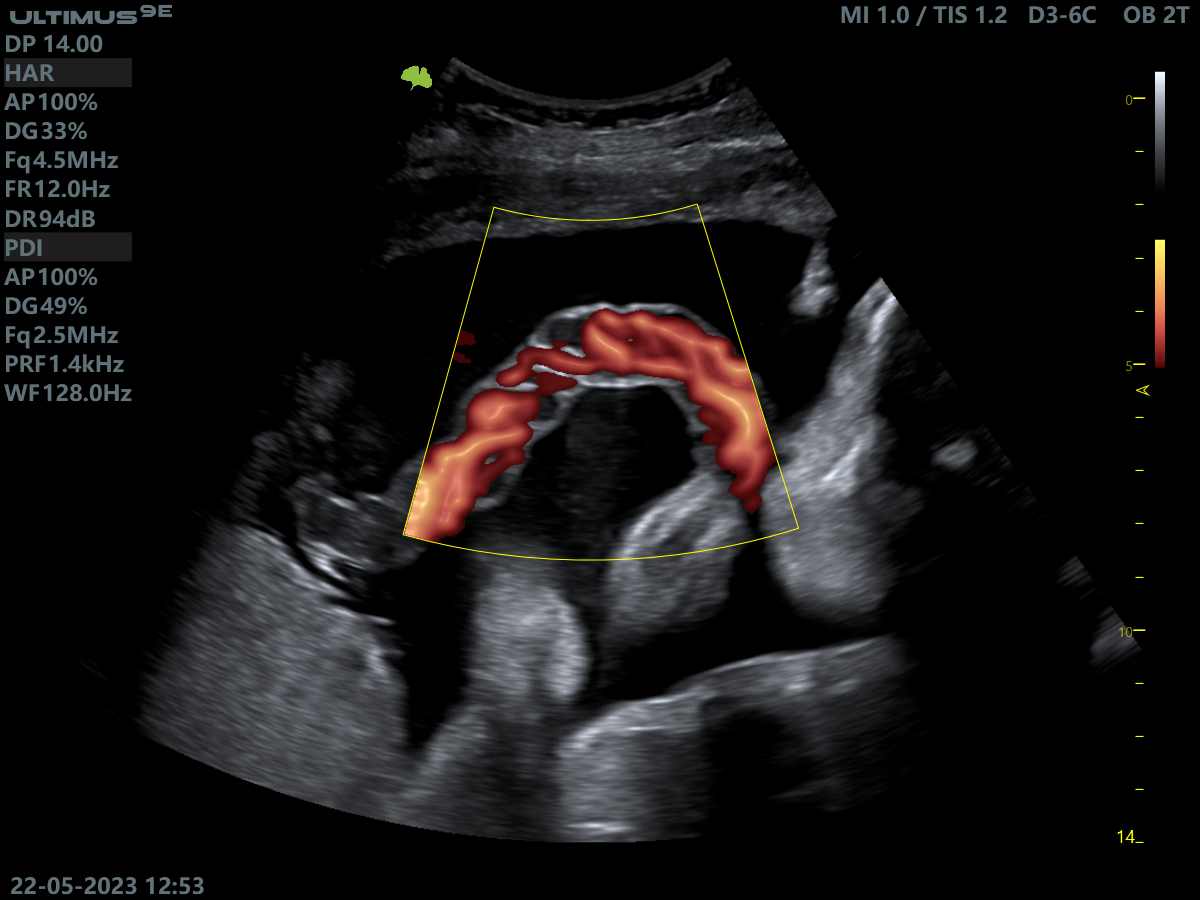

Клінічні зображення, що демонструють якість діагностики та можливості обладнання

Клінічне зображення 3

Клінічне зображення 4